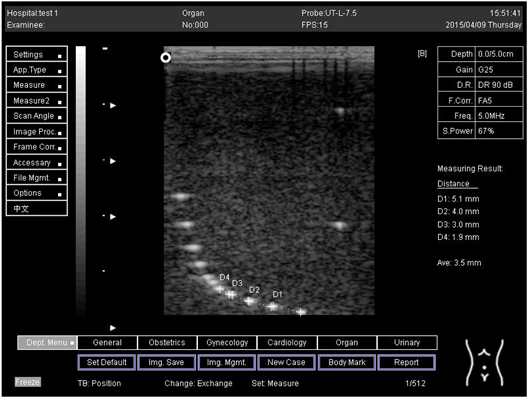

9.0 Axial resolution

Biomimetics 07 00130 i001

D1 = 4.9

D2 = 4.1

D3 = 3.1

D4 = 2.2

Lateral resolution

Biomimetics 07 00130 i002

D1 = 5.0

D2 = 4.0

D3 = 3.0